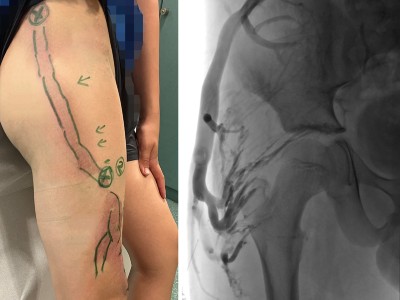

Was kann die Gefäßchirurgie bei vaskulären Malformationen leisten?

Aufgrund ihrer Seltenheit sehen die meisten Gefäßmediziner vaskuläre Malformationen nur vereinzelt. Therapiert werden kann die „orphan disease“ medikamentös, interventionell und operativ, Leitlinien fehlen. Das macht eine Behandlung nicht einfacher. In diesem Artikel werden Ihnen Fälle präsentiert, in denen die Chirurgie die Therapie der Wahl darstellt.

Marginalvene Typ IV/© Gebhardt C et al. / all rights reserved Springer Medizin Verlag GmbH, OCT der Papille am linken Auge/© Jandewerth T et al. doi.org/10.1007/s00129-024-05289-9 unter CC-BY 4.0, Angiogramm bei Bauchaortenaneurysma/© Belezapoy / Stock.adobe.com, PET-CT Aortenaneurysma/© Novoa Usme M.M. et al. / all rights reserved Springer Medizin Verlag GmbH, Zerebrales Aneurysma/© Springer Medizin Verlag GmbH, Übergabe Notfallpatient vom Rettungsdienst an Notaufnahme/© andresr / Getty Images / iStock (Symbolbild mit Fotomodellen), Arzt übergibt Patient Medikamente/© joyfotoliakid / stock.adobe.com (Symbolbild mit Fotomodellen), Frau mit Tablette und Wasserglas in Händen/© fizkes / stock.adobe.com (Symbolbild mit Fotomodell), Operation/© Tobilander / stock.adobe.com (Symbolbild mit Fotomodellen), Blutdruck messen/© (M) sudok1 / stock.adobe.com, Ernährungssonde im Röntgenbild/© Klinischer Image- und Bilddokumentenfokus der Klinik für Radiologie und Nuklearmedizin; Otto-von-Guericke-Universität mit Universitätsklinikum, Magdeburg, Deutschland, Search Icon, Die Leitlinien für Ärztinnen und Ärzte, Darmpolypen/© Hollenbach M et al. / all rights reserved Springer Medizin Verlag GmbH, Arzt erläutert Mammographie-Befund/© Gorodenkoff / stock.adobe.com (Symbolbild mit Fotomodell), Box mit Tabletten/© ekachai050050 / stock.adobe.com (Symbolbild), Blutabnahme/© Grafvision / stock.adobe.com (Symbolbild mit Fotomodellen)